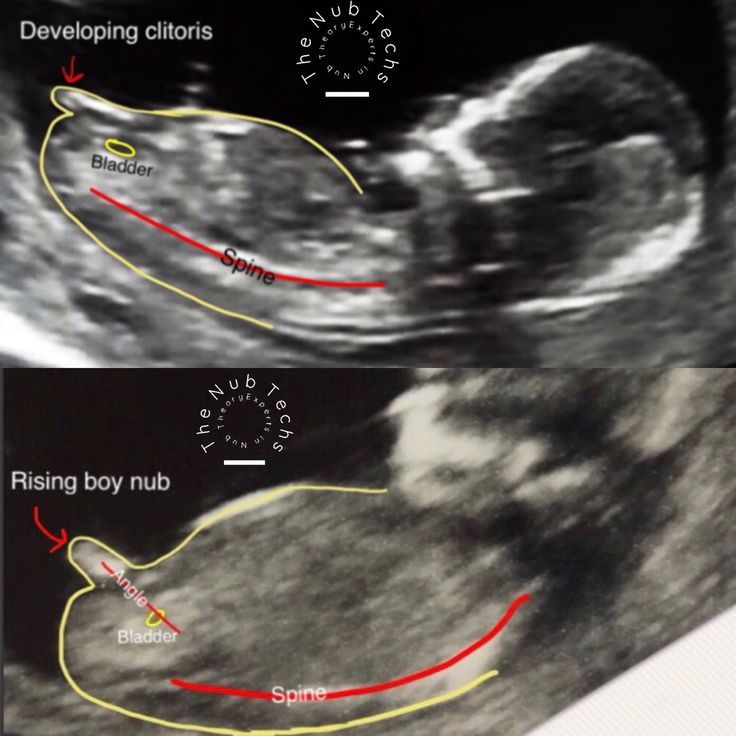

Ксения, вот так. По углу наклона полового бугорка. Снизу на этом сроке смотреть нет смысла - одинаково выглядят, потому что половые органы ещё не сформированы.